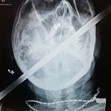

120-сантиметров метален прът пробива главата на моторист, полетял в канавка

Моторист оцеля по чудо след ужасна катастрофа, при която главата му е пронизана от 120-сантиметров метален прът, съобщава Sun.

Опитният мотоциклетист Пол от Скънторп, Линкс карал с приятели от местния мото-клуб,когато загубва контрол и излита в канавка. Там огромен метален кол се забива в главата му.

Медицински хеликоптер го откарва в болница, но не е опериран веднага, защото лекарите са изчакали жена му и двете му деца, за да го видят. Те смятали, че той няма почти никакъв шанс да бъде спасен и семейството му трябва да се сбогува с него.

Какво било обаче учудването им, когато той се възстановил след четиричасовата операция и дори го изписали след 2 дни!